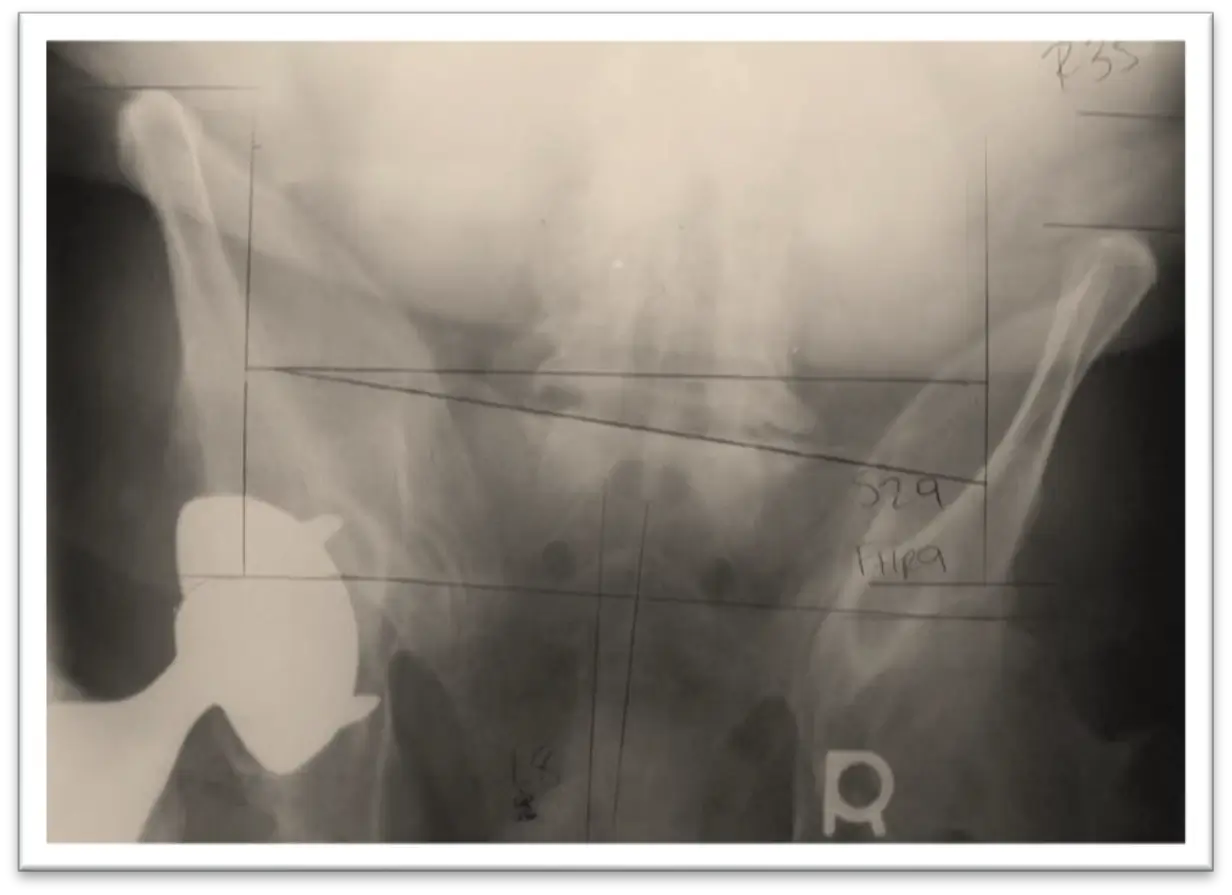

This is a narrowing of the spinal canal (where the spinal cord and descending nerve roots are located) or the intervertebral foramen (where the nerve exits). Stenosis of the spinal canal, often called central stenosis is diagnosed by measuring the size of the canal from front to back. A dimension of 13 mm or more is considered normal. Central stenosis can be congenital or degenerative. Congenital means that it grew that way. Degenerative means that over time wear and tear has caused disc bulging, arthritic development in the joints, swelling of the ligaments or a combination of these factors that has resulted in stenosis.

On the next page are MRI images of a patient with a disc herniation at L5-S1. The before picture clearly demonstrates the disc bulging into the spinal canal. The after picture was taken following a course of treatment including spinal decompression and shows a reduction of the herniation.